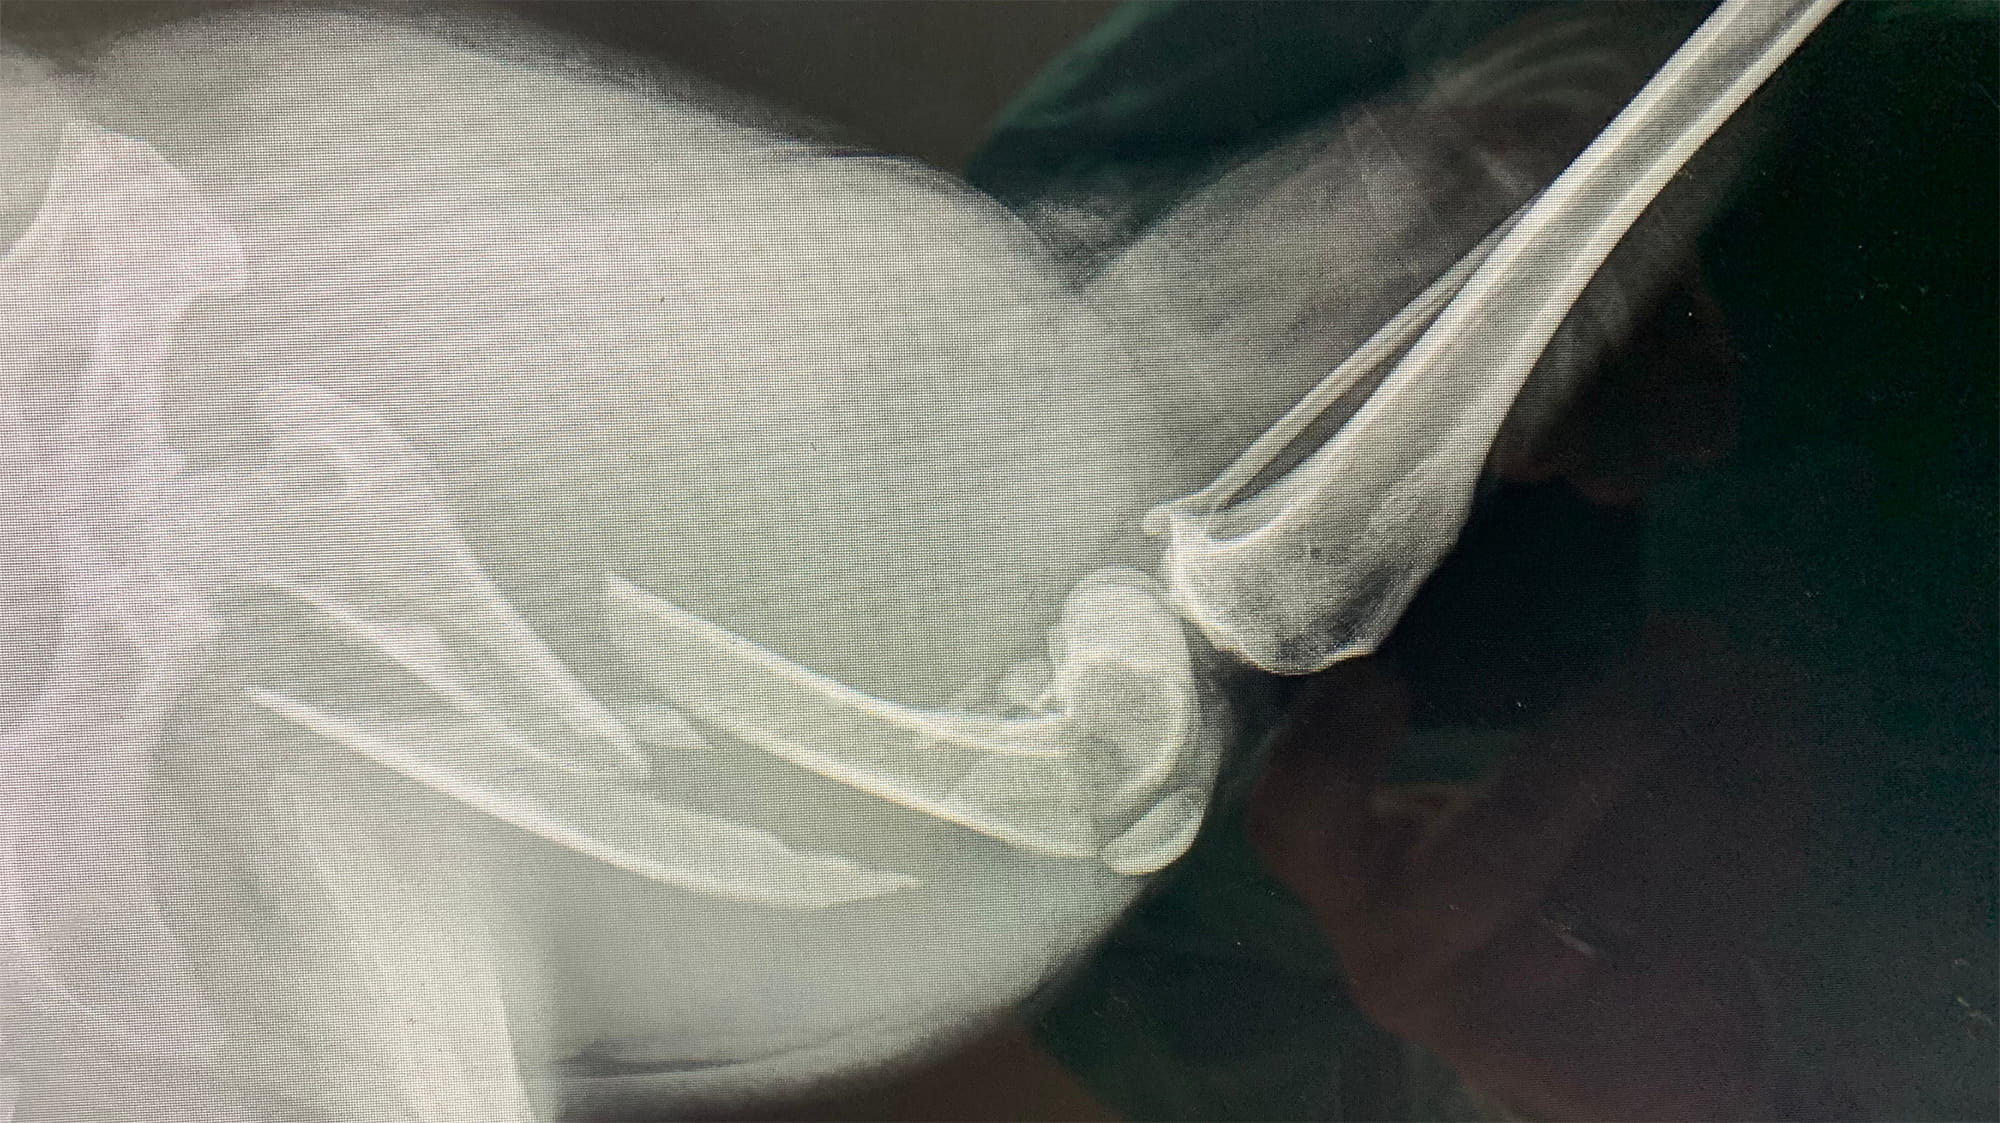

“They did the X-rays, and it showed his femur was broken in three places,” Dona says. “But the doctor said he loved a challenge and that he’d stay with Chevy from start to finish. He wouldn’t amputate, and he would stick to his quote for the cost of surgery no matter what.”

Dr. Beckett confirmed it: He does love a challenge, and Chevy’s leg was just that. Multiple parts of the femur (the thigh bone) were fractured, including the condyle which is part of the knee joint. The X-ray showed three clear breaks, but they ran both up and down as well as side to side. During the one-hour-and-45-minute surgery, however, Dr. Beckett and a young veterinarian discovered seven breaks. Their surgical team used stainless steel metal implants to stabilize the multiple pieces of bone. In the end, Chevy would need extensive surgery to repair the fractures and stabilize the knee joint. Dr. Beckett and his team made it happen with an assortment of medical implants, including rods, plates, screws and wires.